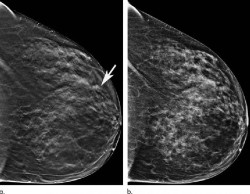

Un equipo internacional de investigadores ha desarrollado un análisis de sangre no invasivo que puede detectar si una persona tiene uno de los cinco tipos comunes de cáncer, estómago, esófago, colorrectal, pulmón e hígado, cuatro años antes de que la afección pueda ser diagnosticada con los métodos actuales, según publican en la revista `Nature Communications`.